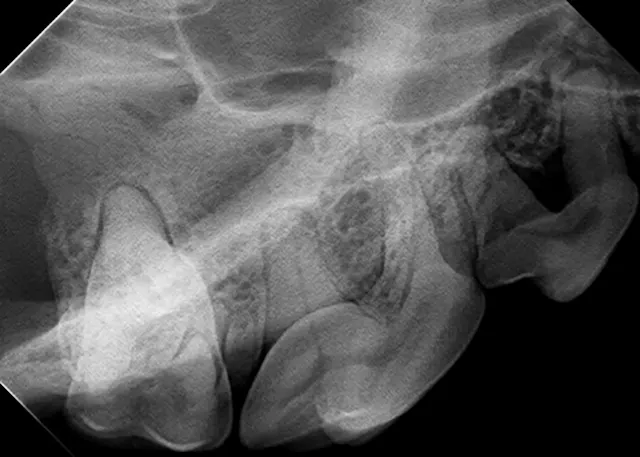

The relatively simple parallel technique is used to image the mandibular caudal cheek teeth on small dogs and cats.

For large dogs, use this technique to image teeth from the third premolar to the last molar. This portion of the oral cavity has room enough to place the sensor parallel and adjacent to the desired teeth, on the lingual aspect of the mandible. Then, aim the tube head perpendicular to the sensor.